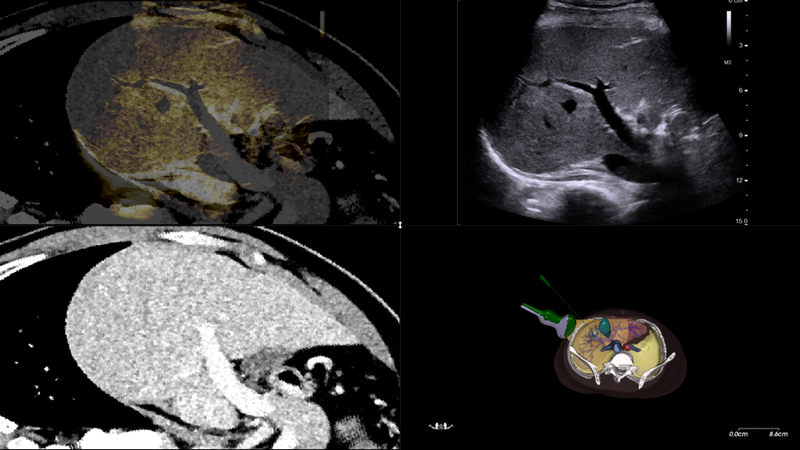

● 全球首创“无外置空间定位系统的实时超声+CT影像融合导航技术”

木星-智能软组织穿刺介入导航手术机器人将术前规划与术中导航的自动结合,可为穿刺和消融治疗提供全流程解决方案。“在软组织穿刺手术导航机器人方向上,我们采用了不依赖于光学和电磁传感器的方案,突破了只靠7自由度机械臂和固定在机械臂末端的超声探头,实现超声影像的3D重建,自动扫描,自主定位和穿刺深度角度的自动调整,并能在穿刺过程中实时监控目标组织。”张博说到。

路径规划可以在穿刺针进入皮肤之前完成的,帮助医生在进针前就预知针的经过路径,从而在路径选择上有效避开重要组织及器官。同时,穿刺路径规划系统也提供了针在组织内的模拟路径规划,能帮助曾经不具备进行肝脏肿瘤穿刺消融手术能力和条件的医院、医院也具备相应能力,赋能基层。

多模态影像融合

受访者供图